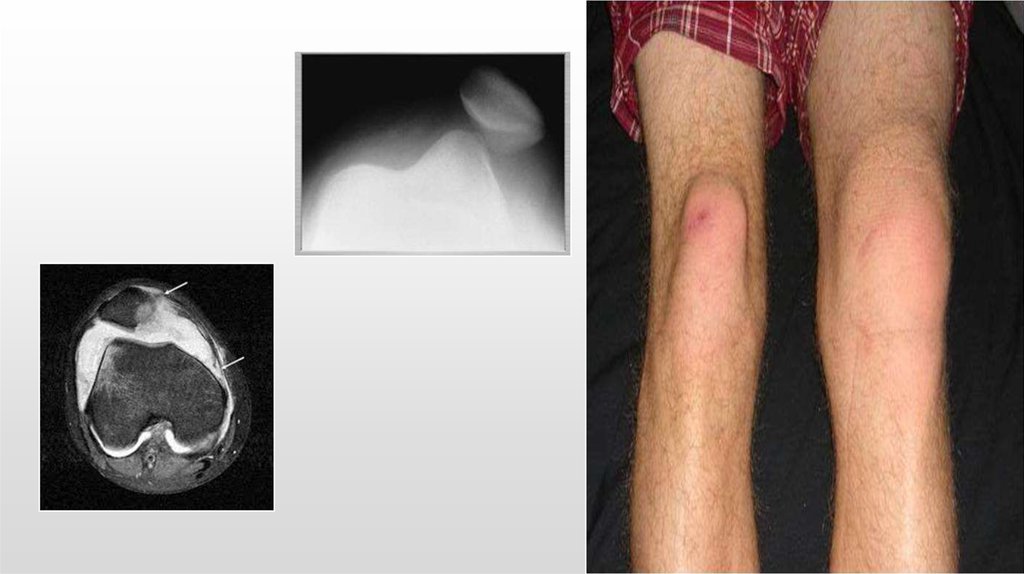

16. Вывих надколенника

17.

18.

19.